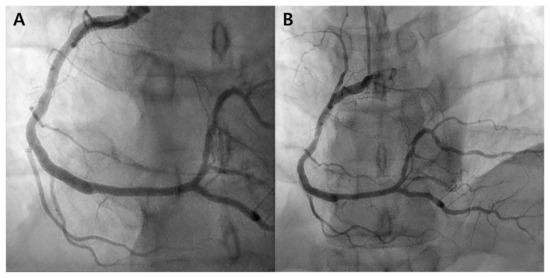

Coronary angiography was performed 1 and 3 years after evolocumab treatment, revealing no target lesion failure or de novo lesions (Figure 3). Presently, the patient maintains medication, is undergoing outpatient follow-up, and is free of specific symptoms.

Figure 3. Follow-up coronary angiography. (A) Right coronary angiography 1 year after evolocumab administration reveals patient stents with no evidence of de novo lesions. (B) Right coronary angiography performed 3 years after evolocumab administration displays no in-stent stenosis or de novo lesions.